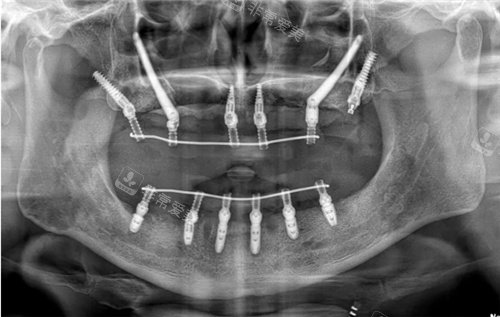

穿颧穿翼CT展示图